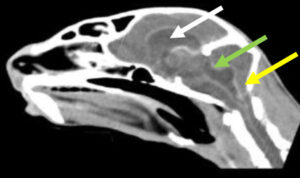

↑ 上の写真は、免疫介在性溶血性貧血の犬の血液塗抹標本。・■ 赤血球の大きさが不均一な大小不同症と、多染性赤血球(多染性赤血球:より大きく好塩基性の未熟な赤血球;緑色の矢印)が認められる。・■ 核を…